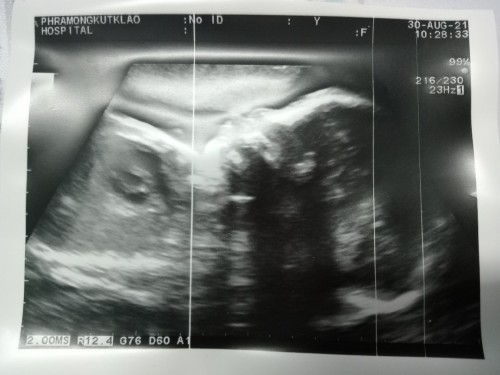

31 +4 weeks ลุงหมอบอกว่าหนูดิ้นเก่งมาก ยุกยิกไม่หยุดเลย ยุกยิกตลอดเวลา น้ำหนักหนู 1600 กรัม แล้วนะ แม่ตรวจน้ำตาลวันนี้ ปกติ พร้อมแล้วนะ เหลือแค่ออกกำลังกายเบาๆ และรอเวลาหนูออกมาอย่างเดียว แม่บวมน้ำ น้ำอยู่ที่แม่หมดเลย หนูปกติทุกอย่าง แต่แม่เกินทุกอย่างเลย 5555 ใกล้ได้เจอกันแล้วนะเด็กอ้วน แม่กับพ่อเฝ้ารอหนูทุกวันเลยนะ #น่านฟ้าตัวแสบ #บันทึกของน่านฟ้า ❤️